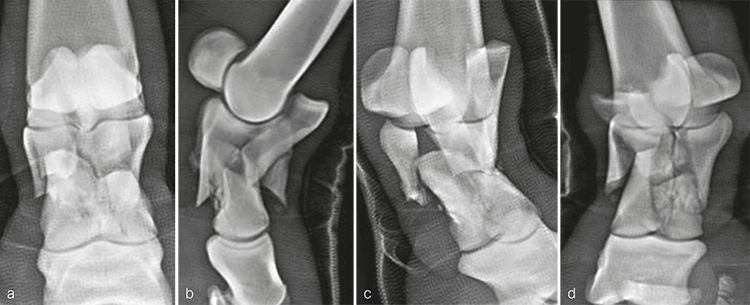

A 14-year-old Belgian warmblood mare weighing 520 kg was presented with a medical history of severe right forelimb lameness following an unwitnessed paddock injury. Radiographs confirmed a highly comminuted fracture of P1. A distal limb bandage had been applied in an attempt to stabilize the injury before transporting the mare.

Radiographic evaluation at the time of admission confirmed the highly comminuted fracture configuration and revealed considerable collapse of P1 with malalignment and overriding of the fracture fragments (Fig 3). Due to the highly unstable nature of the injury and the presence of multiple sharp fracture fragments, the immediate concern was the potential for skin penetration and conversion to an open fracture. Consequently, the mare was placed under general anesthesia to facilitate indirect fracture reduction through traction on the distal limb. Once alignment was confirmed radiographically, the distal limb was stabilized by application of a fiberglass cast extending distally from the proximal metacarpus and incorporating the hoof.

A 10-year-old French warmblood gelding weighing 580 kg was presented a few hours after developing a severe left forelimb lameness following an unwitnessed paddock injury. Initial radiographs demonstrated a severely comminuted, minimally displaced fracture of P1 (Fig 7). The distal limb was immediately placed in a fiberglass cast by the referring veterinarian before transporting the horse, which prevented further displacement of the fragments.